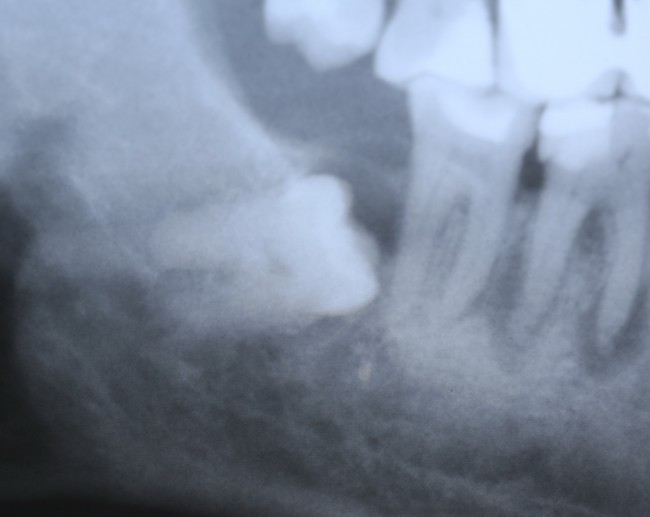

Примерно через три года снимок повторили — уже по другому поводу:

И что мы видим? Под зубом образовалась гигантских размеров фолликулярная киста. То есть, теперь нам нужно не только удалять ретинированный зуб мудрости, но и фолликулярную кисту. А для этого, кстати, придется депульпировать соседний седьмой зуб:

то есть, вместо пустячного и своевременного удаления ретинированной восьмерки, мы получили серьезную проблему, которая, к счастью разрешилась, благодаря случайно сделанному панорамному снимку и вовремя проведенному хирургическому вмешательству.

И хорошо, что это, всего лишь восьмерка — удалили зуб, удалили кисту и забыли о проблеме. Но ретинированный зуб, как и сверхкомплектный, может быть любым и в любом месте. И в случае, если он находится в пределах зубного ряда, нам нужно не только удалять его и образованную им кисту, но и думать о судьбе соседних зубов. Вот пример — гигантская фолликулярная киста, которая привела к потере всех нижних передних резцов: